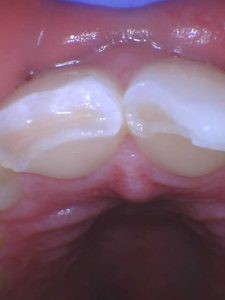

Front teeth fracture

Fortunately, the patient didn’t bite her lips or damage anything else intraorally except for the two upper front teeth. She had a hard time opening or closing her mouth due to the swelling of her upper lip, and she had a lot of sensitivity simply from air or cold on the two broken teeth.

Dr. Whitman took one x-ray of the two front teeth and determined that other than the visible broken areas, there was no fracture of the roots below the gum line. However, the fractures were serious and extended down far onto the back of the teeth, but there was no nerve exposure on either tooth.